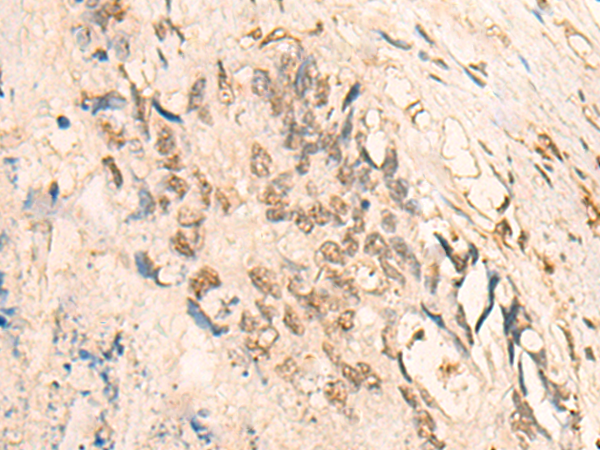

IHC positive control:

Human lung cancer and Human colorectal cancer

IHC Recommend dilution:

25-100